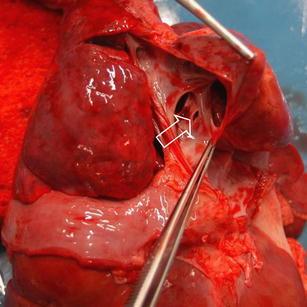

Cerebral arterial air embolism (CAAE) has been reported as a rare complication of medical intervention. There has been one reported case of CAAE after the use of an intraosseous infusion (IO) system. We report on a case of CAAE after tibial IO infusion in a 7-month-old girl during resuscitation.

脑动脉空气栓塞(CAAE)已被报道为一种罕见的医疗干预并发症。曾有一例使用骨内输液(IO)系统后发生CAAE的报告。我们报告一例7个月大女童在复苏过程中经胫骨IO输液后发生CAAE的病例。